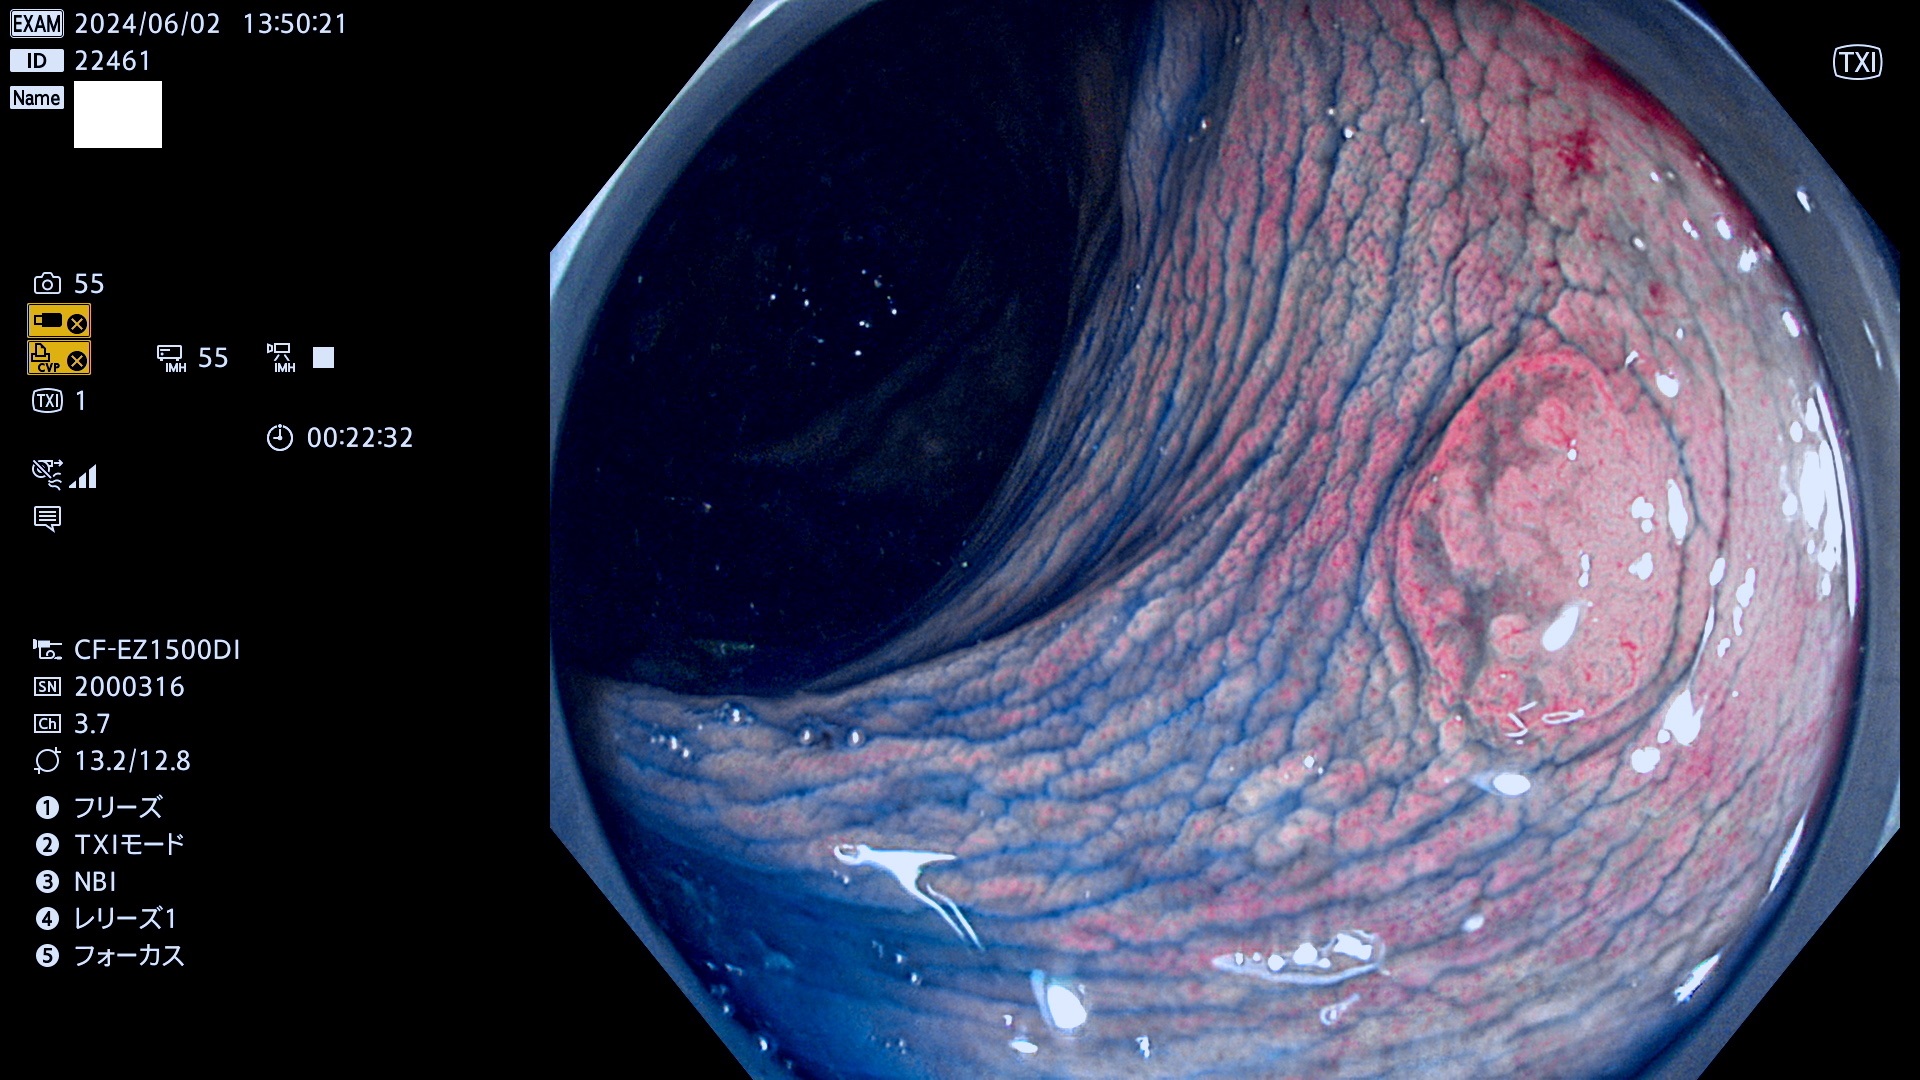

今週のUb、Uc型腺腫

表面型腺腫(Flat Adenoma)の中で、完全に平坦な物をUb、陥凹している物をUcと呼びます。平坦隆起型(Ua)よりも、発見が難しく危険な病変です。

毎週の検査(木・金・土・日)に発見されたUb、Uc型・腺腫を、その週の日曜の夜にUPし1週間、提示します。

抽出の対象期間 2024年5月30日〜6月2の4日間(40件の検査)7件 (7/40=18%)